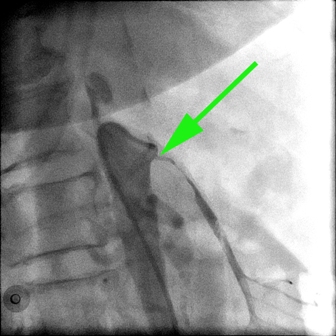

Ангиография. Показано место сужения верхней брызжеечной артерии.